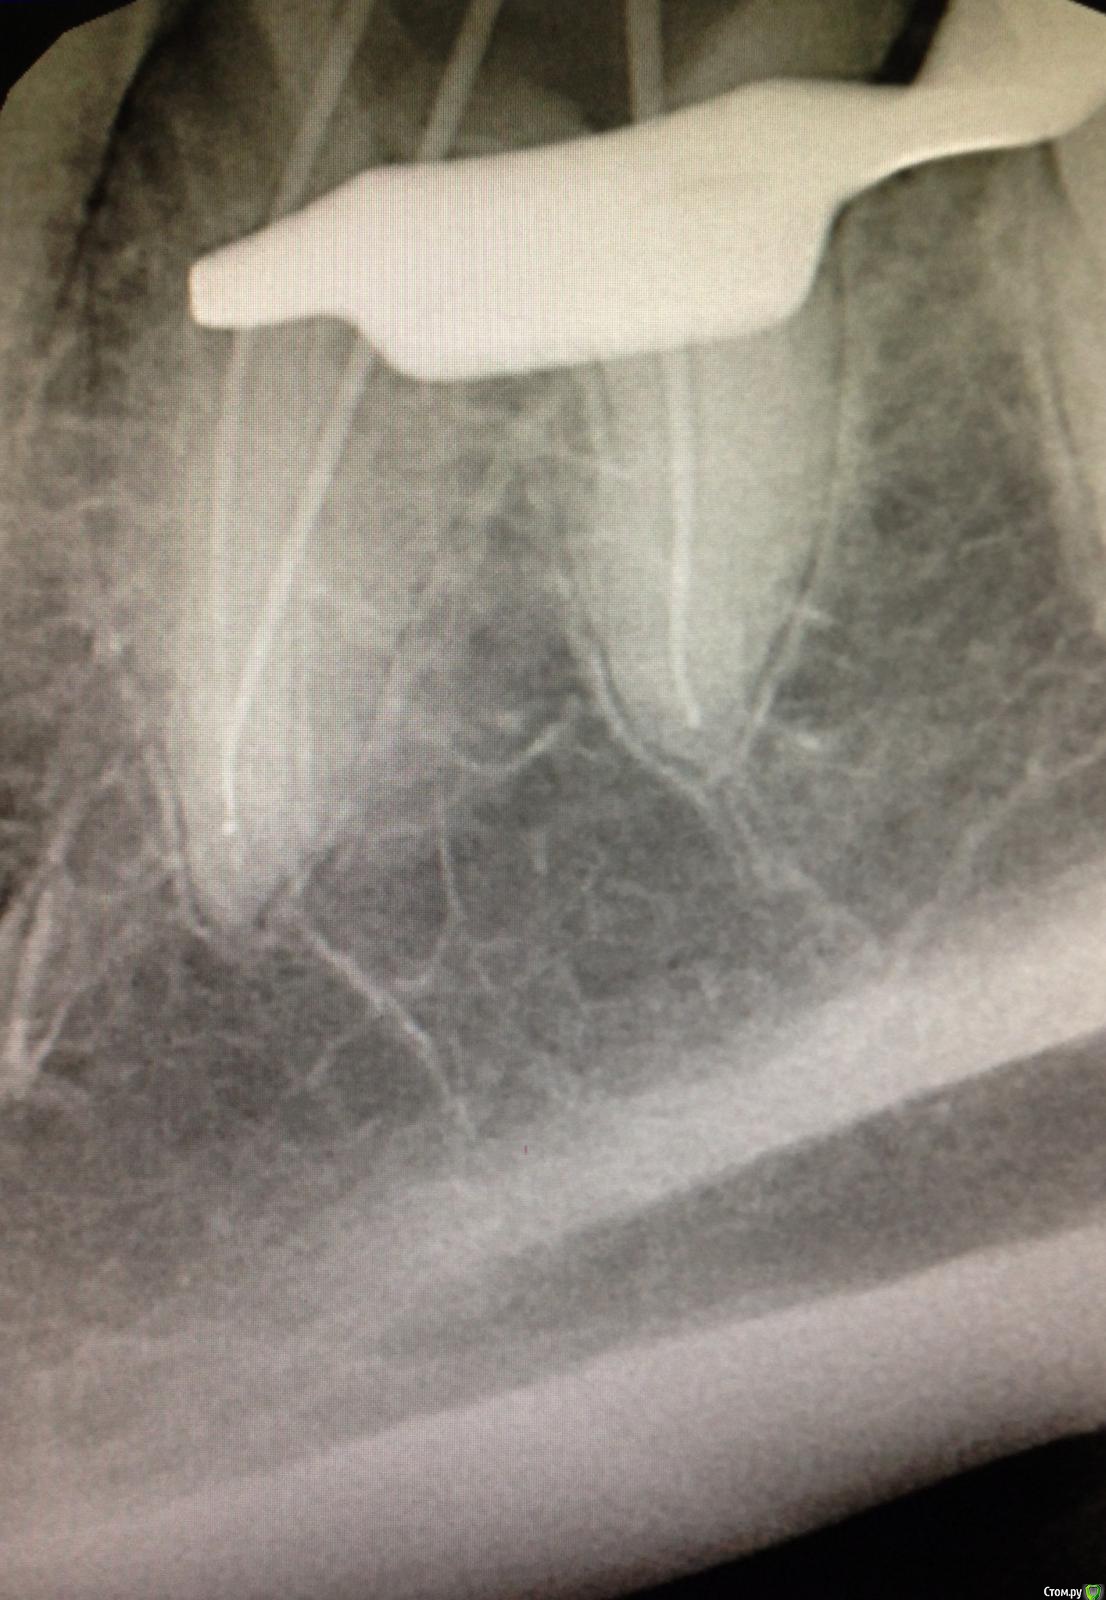

SSTi Опубликовано 9 декабря, 2014 Автор Поделиться Опубликовано 9 декабря, 2014 Чуть обновимся. Пульпитный 36. Медиальные профайлы 35.04. Дистальный 40.04. ОХАП 37. Резорцин старый. Через кальций. 12 хап. 13 пульпит. 60 упор 5 Ссылка на комментарий